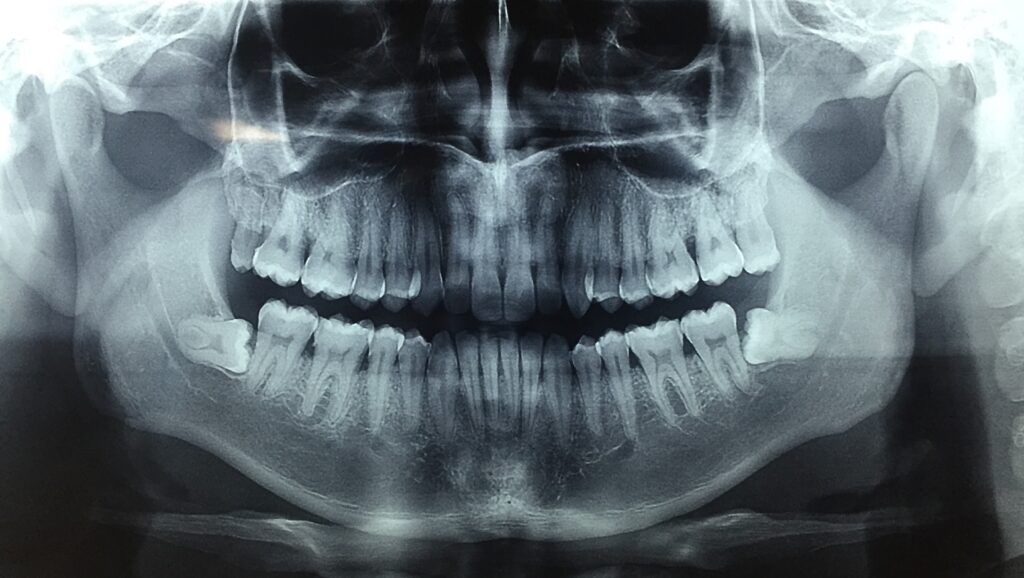

La cirugía de terceros molares o muelas del juicio es un procedimiento quirúrgico menor que se realiza para extraer los últimos dientes de la dentadura. Se recomienda realizarla cuando:

La edad ideal para realizar la extracción es entre los 16 y 18 años, ya que el hueso es más blando y la raíz del molar no está completamente formada.